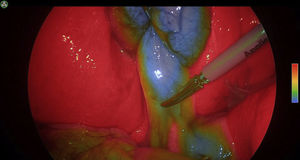

Use of ICG for the identification of anatomical structuresBile ductFluorescence with ICG allows virtual cholangiography to be performed in real time during dissection in laparoscopic cholecystectomy, thereby identifying anatomical variations and avoiding situations of potential risk of bile duct injury.

When ICG concentrates at the liver and is excreted through the bile, it makes it possible to outline the anatomy of the biliary tree and the junction between the cystic and the common hepatic ducts.31

One of the associated problems is that the high fluorescence of the liver can prevent or hinder the identification of the biliary tree and, especially if the injection has been very recent, prevents correct visualization of the bile duct.30 To avoid these issues, some authors have proposed earlier preoperative injection or direct gallbladder injection,31–33 although it is a somewhat cumbersome technique and not always possible. For the reasons previously mentioned and for perfect definition of the bile duct with less hepatic contrast, ICG should be administered 3−8 h before surgery,29–34 although new vision systems enable injection even during anesthesia induction (Fig. 2).